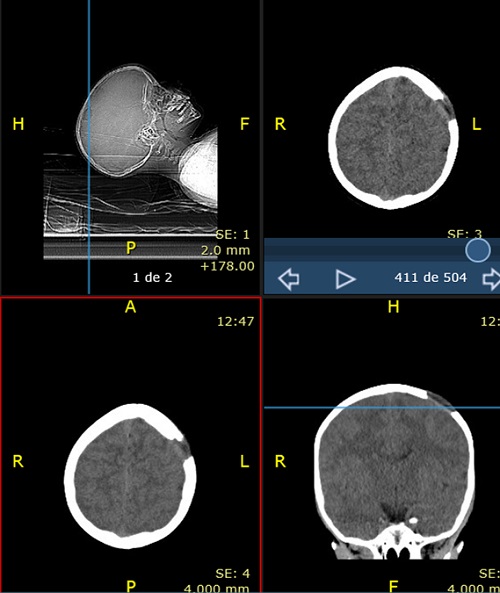

Paciente de 4 años que acude con su madre a consulta por bultoma en cuero cabelludo descubierto de forma casual 7 días antes, sin relación con antecedente traumático y con dolor a la palpación. Desde entonces presenta despertares nocturnos con irritabilidad, que mejoran con analgésicos. Antecedentes familiares y personales sin interés. Desarrollo madurativo normal. Vacunas adecuadas para su edad. No alergias conocidas. El paciente presenta muy buen estado general, apirético y con exploración normal, tanto somática como neurológica, salvo tumoración de consistencia blanda en región parietal izquierda de 2,5-3 cm de diámetro, dolorosa a la palpación. Se deriva al hospital de referencia para pruebas de imagen. La Rx de cráneo muestra una lesión osteolítica en sacabocados, posiblemente compatible con GE (Figura 1). Rx de tórax, serie ósea y ecografía abdominal normales. TAC craneal evidencia los mismos signos (Figura 2). La RMN detecta una lesión única intraósea expansiva parietal izquierda, que atraviesa la tabla ósea externa e interna con mínimo engrosamiento, e hipercaptación de la duramadre subyacente, sugerente de GE como primera posibilidad radiológica. Hemograma y bioquímica dentro de la normalidad.

Figura 1. Radiografía lateral de cráneo